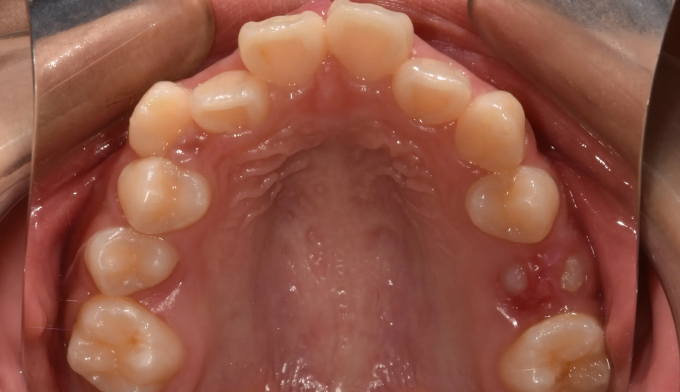

위턱, 아래턱 모두 치아 배열 공간이 부족한 경우 입니다.

확장장치를 이용해 공간 부족을 해결하고 치열을 배열하면 간단히 끝낼 수 있습니다.

이때 입술의 두께나 위치, 위아래 앞니의 각도를 종합적으로 고려하여야 합니다.

치아를 배열한다고 앞니가 뻐드러지면 잘못된 교정치료입니다.

총 치료기간은 20개월 소요되었습니다.